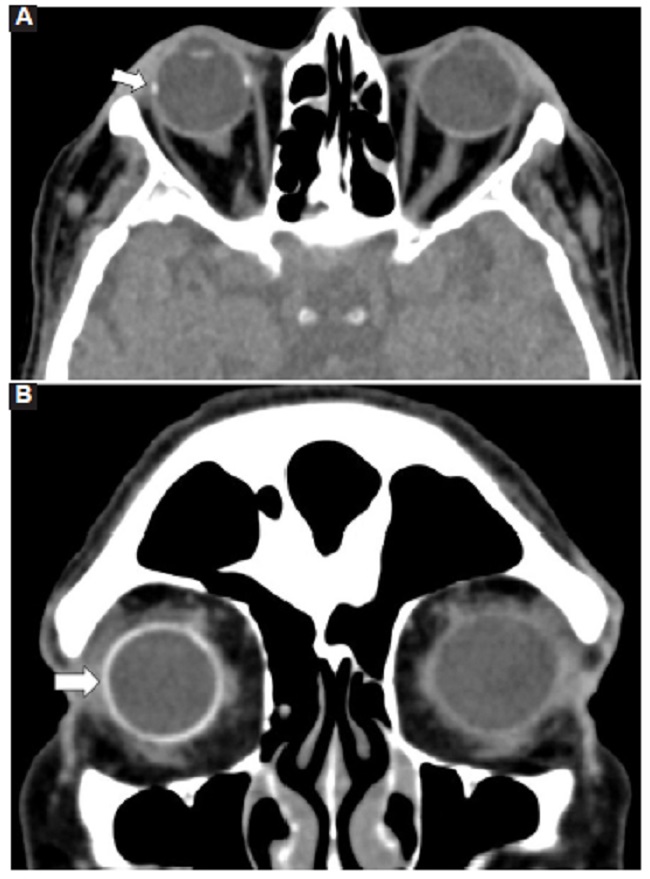

Las calcificaciones oculares y el material médico se pueden confundir con cuerpos extraños u otras lesiones orbitarias1. Las localizaciones típicas de las calcificaciones permiten diferenciarlas de cuerpos extraños hiperdensos. Las más frecuentes son las calcificaciones trocleares, las placas esclerales, las drusas del nervio óptico y la ptisis bulbi. Las primeras tienen localización superomedial dentro de la órbita (Fig. 13), en la tróclea del músculo oblicuo superior, aunque se pueden observar en todas las edades, hay mayor prevalencia de calcificaciones trocleares en pacientes con enfermedades autoinmunes y niveles elevados de fosfatasas alcalinas. Las placas esclerales se localizan en los sitios de inserción de los músculos rectos medial y lateral (Fig. 14) y son más comunes en los pacientes ancianos. Las calcificaciones que ocurren cerca del disco óptico se conocen como drusas del nervio óptico (Fig. 15), las cuales se asocian a degeneración macular y pueden ser causa de pseudopapiledema benigno. La ptisis bulbi es una atrofia y calcificación del globo ocular como secuela de enfermedades infecciosas, inflamatorias o traumáticas previas (Fig. 16) (1,11. Los imitadores de lesiones abiertas del globo ocular incluyen las deformidades como coloboma, estafiloma y el globo ocular elongado por glaucoma o miopía (Fig. 17). Las masas orbitarias y los hematomas también pueden alterar el contorno del globo ocular y asociarse a calcificaciones o relacionarse con desprendimiento de retina (Fig. 18) (1,6,8,11.

Los cambios postratamiento y los dispositivos orbitarios también pueden malinterpretarse como patologías traumáticas. Dentro de estos cambios se incluyen la faquectomía con reemplazo del cristalino, las hebillas esclerales (Figs. 19 y 20), las inyecciones intraoculares de aceite de silicona, la retinopexia neumática y las prótesis de globo ocular1,6,11. Para diferenciar la silicona intraocular de hemorragia se ha propuesto la medición de las UH, siendo la atenuación > 100 UH sugerente de silicona y < 90 UH de sangre11 (Fig. 20).